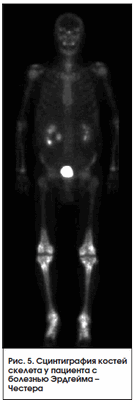

Болезнь Эрдгейма - Честера

Является редким заболеванием. Может рассматриваться как опухолевое или воспалительное заболевание и характеризуется инфильтрацией органов нелангенгарсовыми гистиоцитами. Чаще всего не диагностируется, хотя имеет патогномоничную сцинтиграфическую картину. При сцинтиграфии всего тела c Тс-99m выявляется симметричное повышение накопления РФП в концах длинных трубчатых костей нижних, а иногда и верхних конечностей [6] (рис. 5).